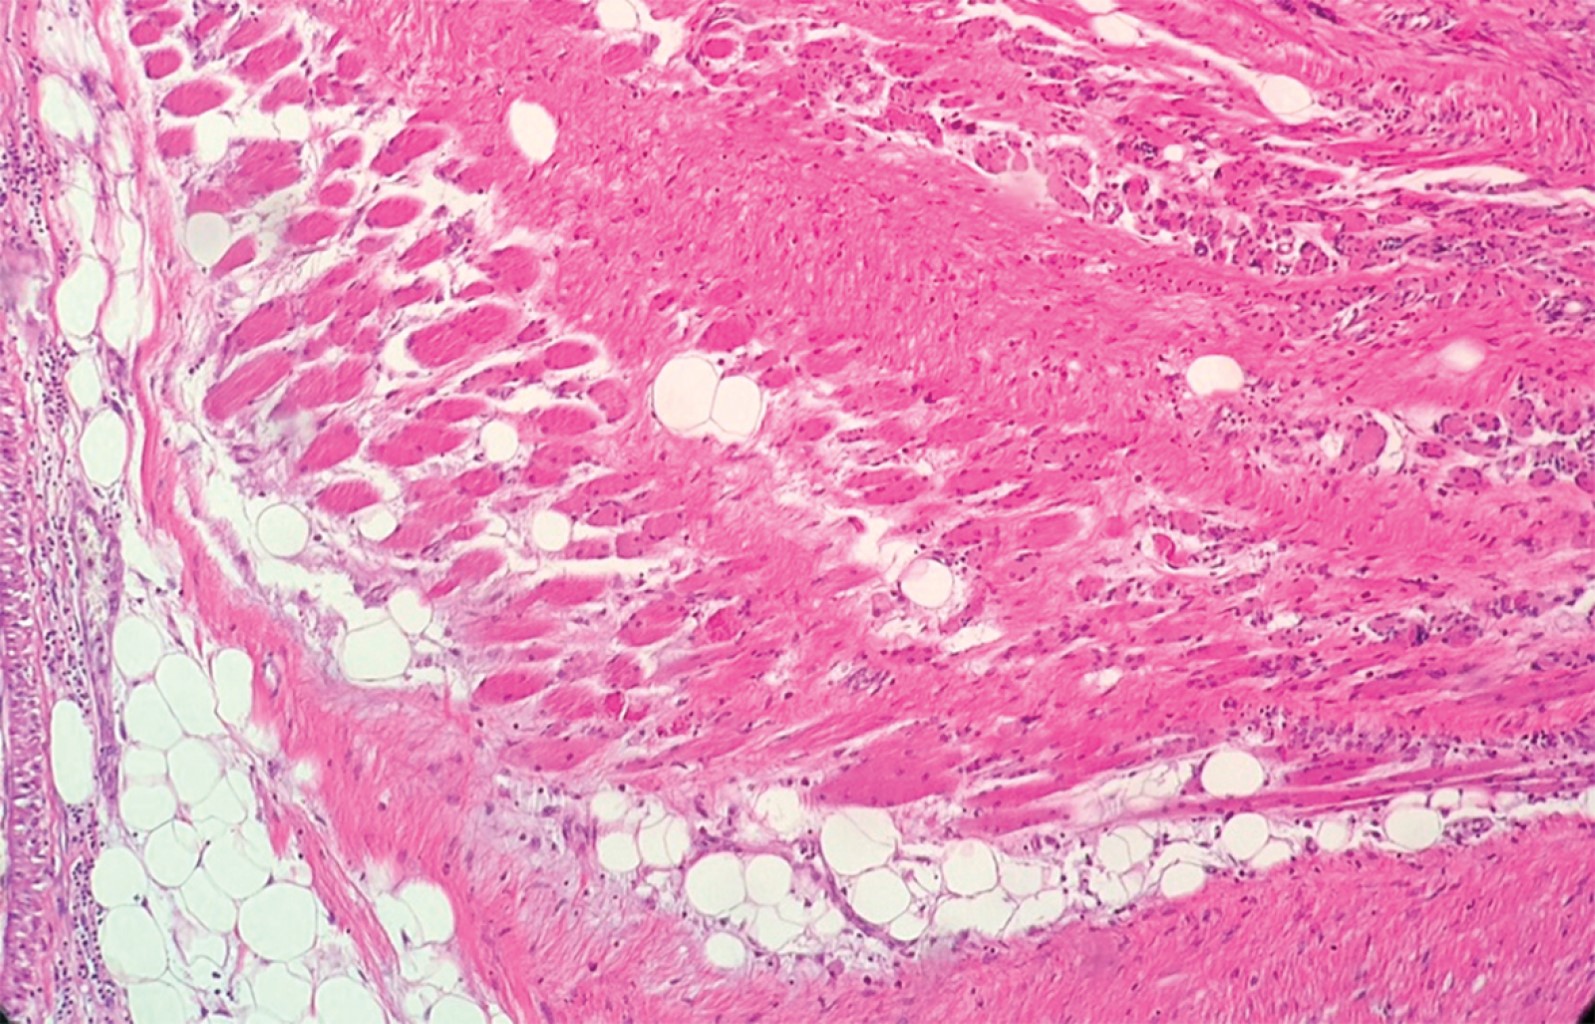

El reporte histopatológico (RHP) indica neoplasia con borde quirúrgico anterior en contacto con la neoplasia y los demás márgenes libres que respeta la vena y arteria subclavias; el reporte definitivo describe histológicamente una proliferación celular no atípica, sin evidencia de mitosis, con elementos proliferantes de tipo fusiforme con colagenización intercelular y que infiltran el tejido adiposo y muscular en la periferia (Figuras 4, 5 y 6).